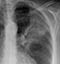

COPD – Hyperexpansion

- In normal subjects the diaphragm is intersected by the 5th to 7th anterior ribs in the mid-clavicular line

- It is often difficult to see the ribs in patients with COPD as they are osteopenic due to long term steroid use - as in this patient

- In this image, the 7th ribs, which are only just visible, intersect the diaphragm (red lines) level with the mid-clavicular line – so are the lungs hyperexpanded?

- Patient positioning and use of accessory muscles of respiration can influence the anatomical positioning of the ribs on a chest X-ray

- Flattening of the diaphragm (red lines) is often a more reliable feature of lung hyperexpansion

- The green dotted lines indicate the predicted normal diaphragm shape and position